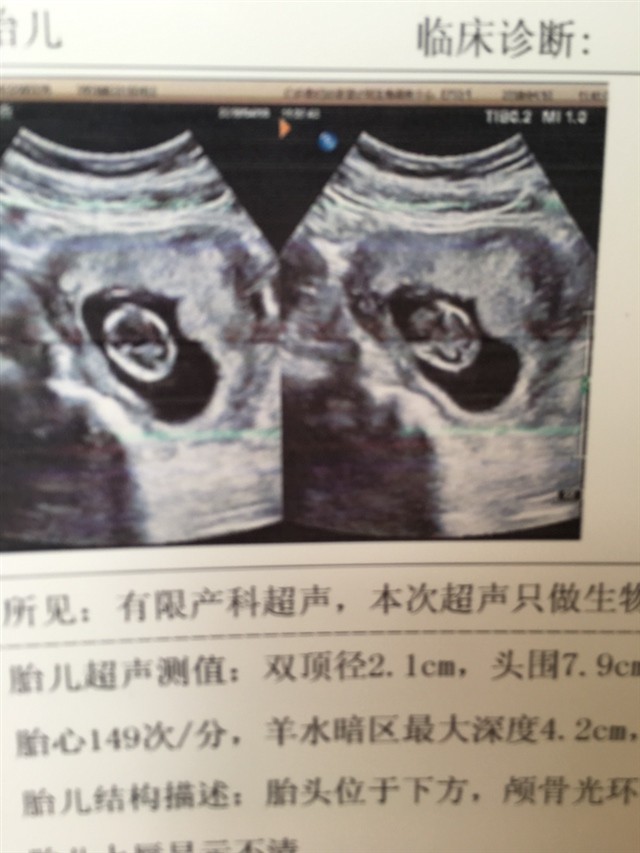

孕26周+4天